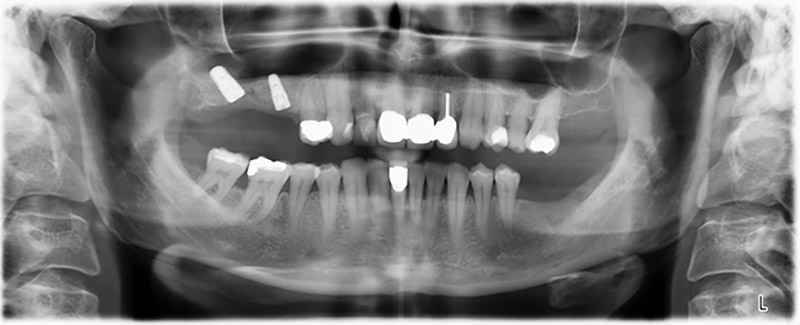

The 59-year-old patient presented with an advanced case of periodontitis, describing an unpleasant feeling and poor taste from the first quadrant in a distal direction. The clinical examination revealed generally enlarged periodontal pockets and very advanced bone atrophy in regions 16 and 14. The radiology confirmed the findings (Fig. 1). Teeth 16 and 14 could not be retained.

Image 1: Orthopantomogram with bone atrophy in region 16–14. *